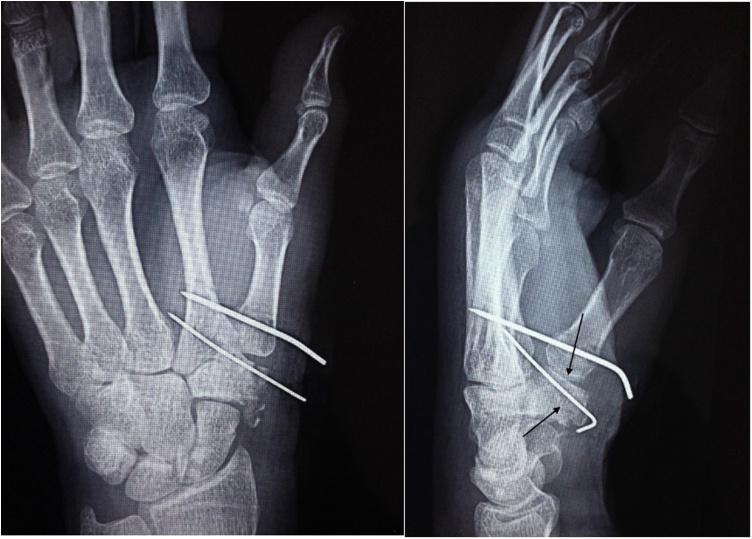

We present a case with an isolated comminuted trapezium fracture presenting pain in his thenar eminence and thumb motion limitation. He was treated by Open Reduction and Internal Fixation (ORIF) with the K wire pin.

我们报告1例孤立性粉碎性大多角骨骨折病例,患者大鱼际隆起处疼痛,拇指活动受限。采用克氏针切开复位内固定(ORIF)治疗。